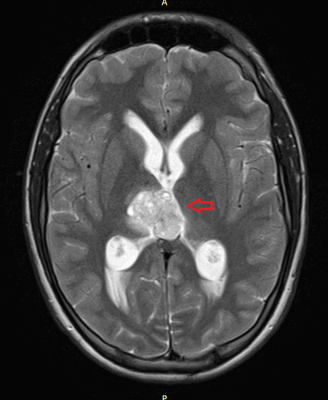

Головной мозг

Герминогенные новообразования в данной области - это примерно 2-4% от всех внутричерепных (интракраниальных). Патология в 75% случаев диагностируется у мальчиков, за исключением турецкого седла, где новообразования в основном локализуются у девочек.

Герминомы формируют инфильтрирующие опухоли больших размеров, часто являющиеся источниками субарахноидальных (между мягкой и паутинной оболочками мозга) и вентрикулярных (желудочковых) метастаз.

Рисунок 7. - Герминома головного мозга.

Рисунок 9. - метастаз в головной мозг при герминогенной опухоли.

Лечение

Герминогенные опухоли центральной нервной системы (головного мозга) имеют следующие клинические проявления: головная боль, расстройство движений глазных яблок, тошнота, рвота и развитие судорог.

Также выполняют МРТ головного мозга, чтобы выявить наличие метастазов в нем.